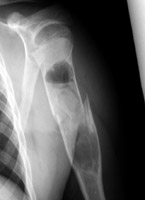

Unicameral bone cyst

Two radiographs of a pathologic fracture in a simple bone cyst of the proximal humerus. Within the cyst is noted a small, thin, linear bony fragment which is displaced from the site of the fracture. An excellent sign of unicameral bone cyst. The fallen fragment secondary to pathologic fracture is pathognomonic for this cyst. A portion of the wall of the cyst has undergone a pathological fracture and subsequently floated down (fallen) via gravity into the dependent portion of the cyst.

- Click on the image for a larger versionA - Click on the image for a larger versionB